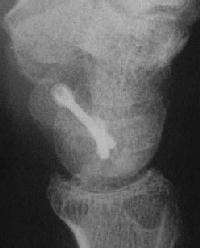

Case 7. This nonunion patient's scaphoid and iliac crest were unusually soft bone.

Click for larger image

After two screws, the fixation was clearly inadequate, so I put a third screw through the graft into the proximal pole. I wasn't sure whether to buy

stock in Herbert screws or Zantac. The fracture healed despite AWOL and no immobilization.